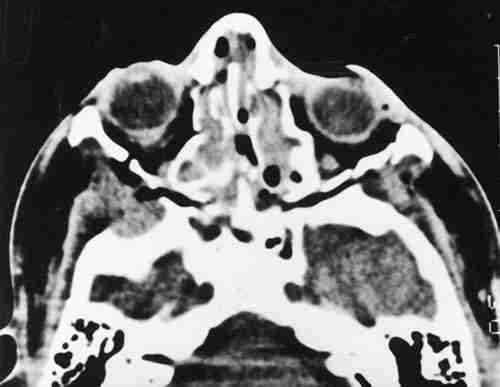

Figura 1

T.A.C. ORBITARIA DONDE SE APRECIAN MÚLTIPLES FRACTURAS FACIALES Y ORBITARIAS.